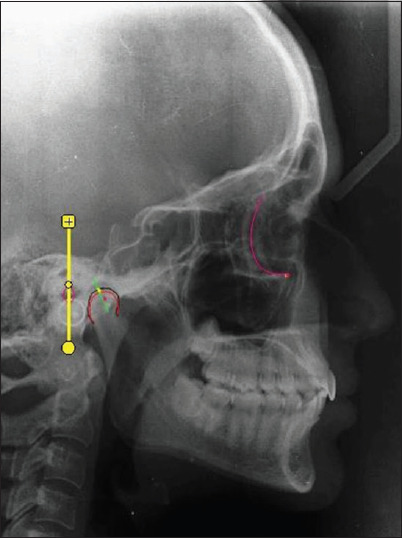

Materials and methods: Twenty-five dentate subjects participated in this study. Customized guides with calibrations at 2, 4, 6, and 8 mm were used to create protrusive interocclusal records at each increment. The HCG values derived from these records were set on a fully adjustable articulator (Denar D5A, Whip Mix Corp.). For control, standardized digital lateral cephalograms of each subject were taken in edge-to-edge and maximal intercuspal positions. These cephalograms were superimposed using Dolphin Imaging software (Dolphin Imaging and Management Solutions), allowing the determination of the cephalometric HCG angle by measuring the intersection between a line passing from the Condylion and the Frankfort horizontal plane. The HCG values from the articulator were compared with the cephalometric HCG values.